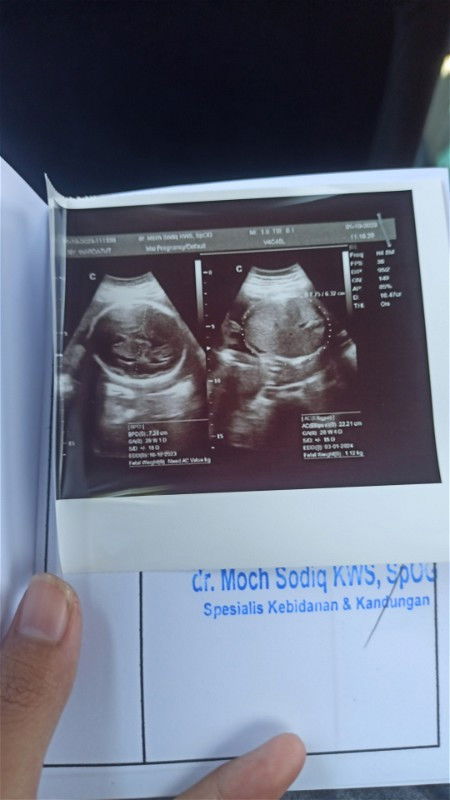

Hy bunda yang sedang hamil 28 week dan memiliki bbj 1,2 kg . Kira² itu normal apa kebesaran ya, soalnya di usg UK jadi 29 week.. Oiya yang dulunya pernah hamil 28 week dengan bbj segitu kira² nanti pas lahir bb anaknya brp kg ya ? Soalnya trauma kehamilan anak pertama yang berat lahirnya 3,7 tidak bisa lahiran normal krn ga kuat ngeden hihi.. #seriusnanya